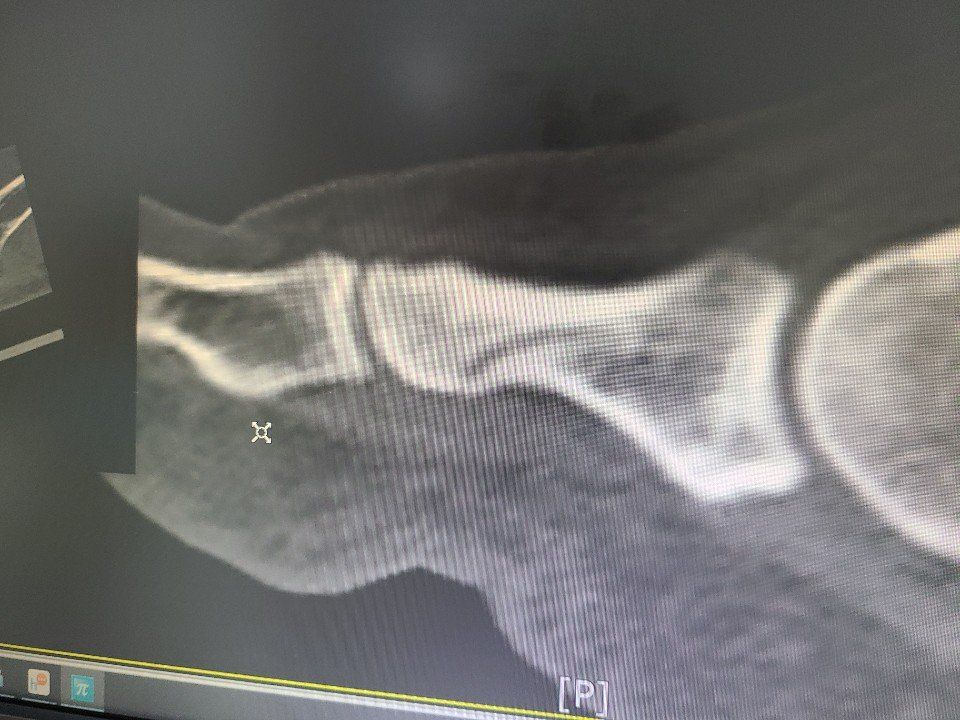

엄지발가락 골절 입니다 수술을이 필요한가요?

왼쪽 엄지발가락이 엑스 레이상 잘 안 나와서 CT를 찍었더니

골절 이라고 합니다

수술 하자고 핀이나 나사로 고정하면 한달 치료되고

안하고 반 깁스하면 두달 걸린다고 합니다

수술 안한다고 했더니 일주일 경과를 보자고 하셨습니다

어떻게 해야 하나요??? 반깁스하고 뒷꿈치로 걸었더니 허리와 목에 무리가 와서

조금 통증이 있습니다 (현재 목56,67 디스크 치료중임)

그리고 깁스 말고 골절부 발가락만 철로 고정 할 수 없나요????

• 1번 째 사진